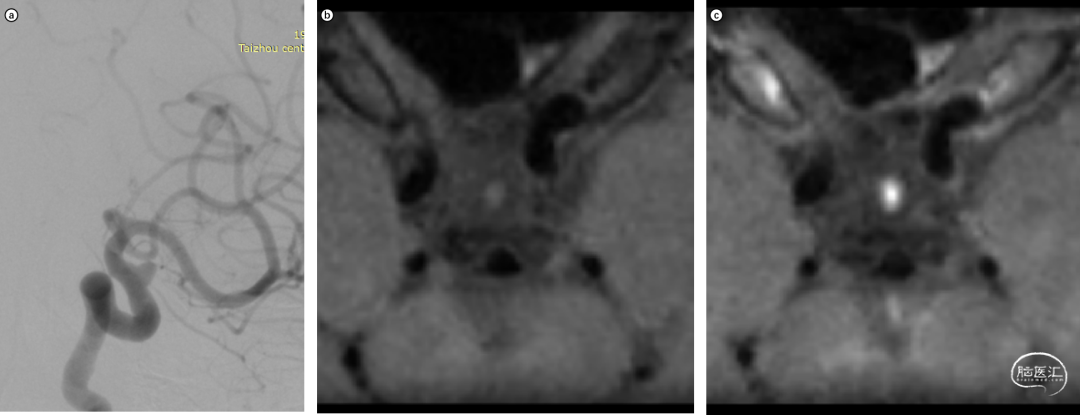

术前诊断

图1. a,b,c:患者为60岁女性,DSA造影显示左侧颈内动脉C6段前壁宽颈动脉瘤,高分辨MRI提示动脉瘤管壁有强化。